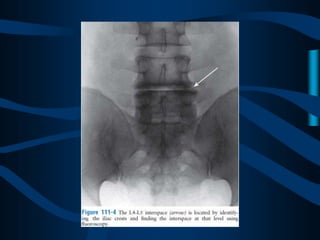

ABORDAJE

TRANSDISCAL

CON UNA AGUJA